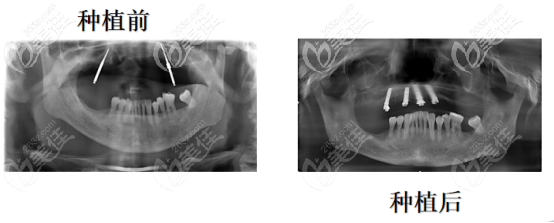

4顆半口諾貝爾種植牙圖片(來自一位60多歲的老人)

胡爺爺是一名退休公務(wù)員,8年前做了烤瓷牙,但是時間太久了,烤瓷牙全壞了,為了方便吃飯,選擇戴的半口活動假牙,但是假牙戴的時間久了,把好牙也磨損的壞了,現(xiàn)在上半口牙齒幾乎全無。

主訴:上半口牙僅剩兩顆,且已經(jīng)松動,咀嚼力差,進(jìn)食困難,需進(jìn)行上半口種植。

胡爺爺上頜骨萎縮的比較厲害,頻繁掉牙,考慮到胡爺爺年齡和牙齦的條件,我們選的是諾貝爾種植體,因為由于胡爺爺怕疼,所以進(jìn)行了數(shù)字化微創(chuàng)種植。

4顆半口諾貝爾種植牙制定方案的過程:借助口腔CT,然后用計算機(jī)模擬胡爺爺面部三維模型,分析牙槽骨骼情況以及面部神經(jīng)和血管的走向,模擬植入種植體,觀察種植體的受力角度和臨牙的位置,確定好咬合關(guān)系之后,設(shè)計種植方案。

給胡爺爺較大程度上保留了他自己的軟組織和骨骼,當(dāng)天出了方案之后就安裝了4顆基臺和牙冠、他當(dāng)天晚上就可以吃飯了。

對胡爺爺進(jìn)行一年的效果追蹤得出的結(jié)論:

1、咬合平衡和垂直的距離沒有發(fā)生變化

2、諾貝爾種植體非常牢固

3、垂直方向的骨吸收小于0.2mm